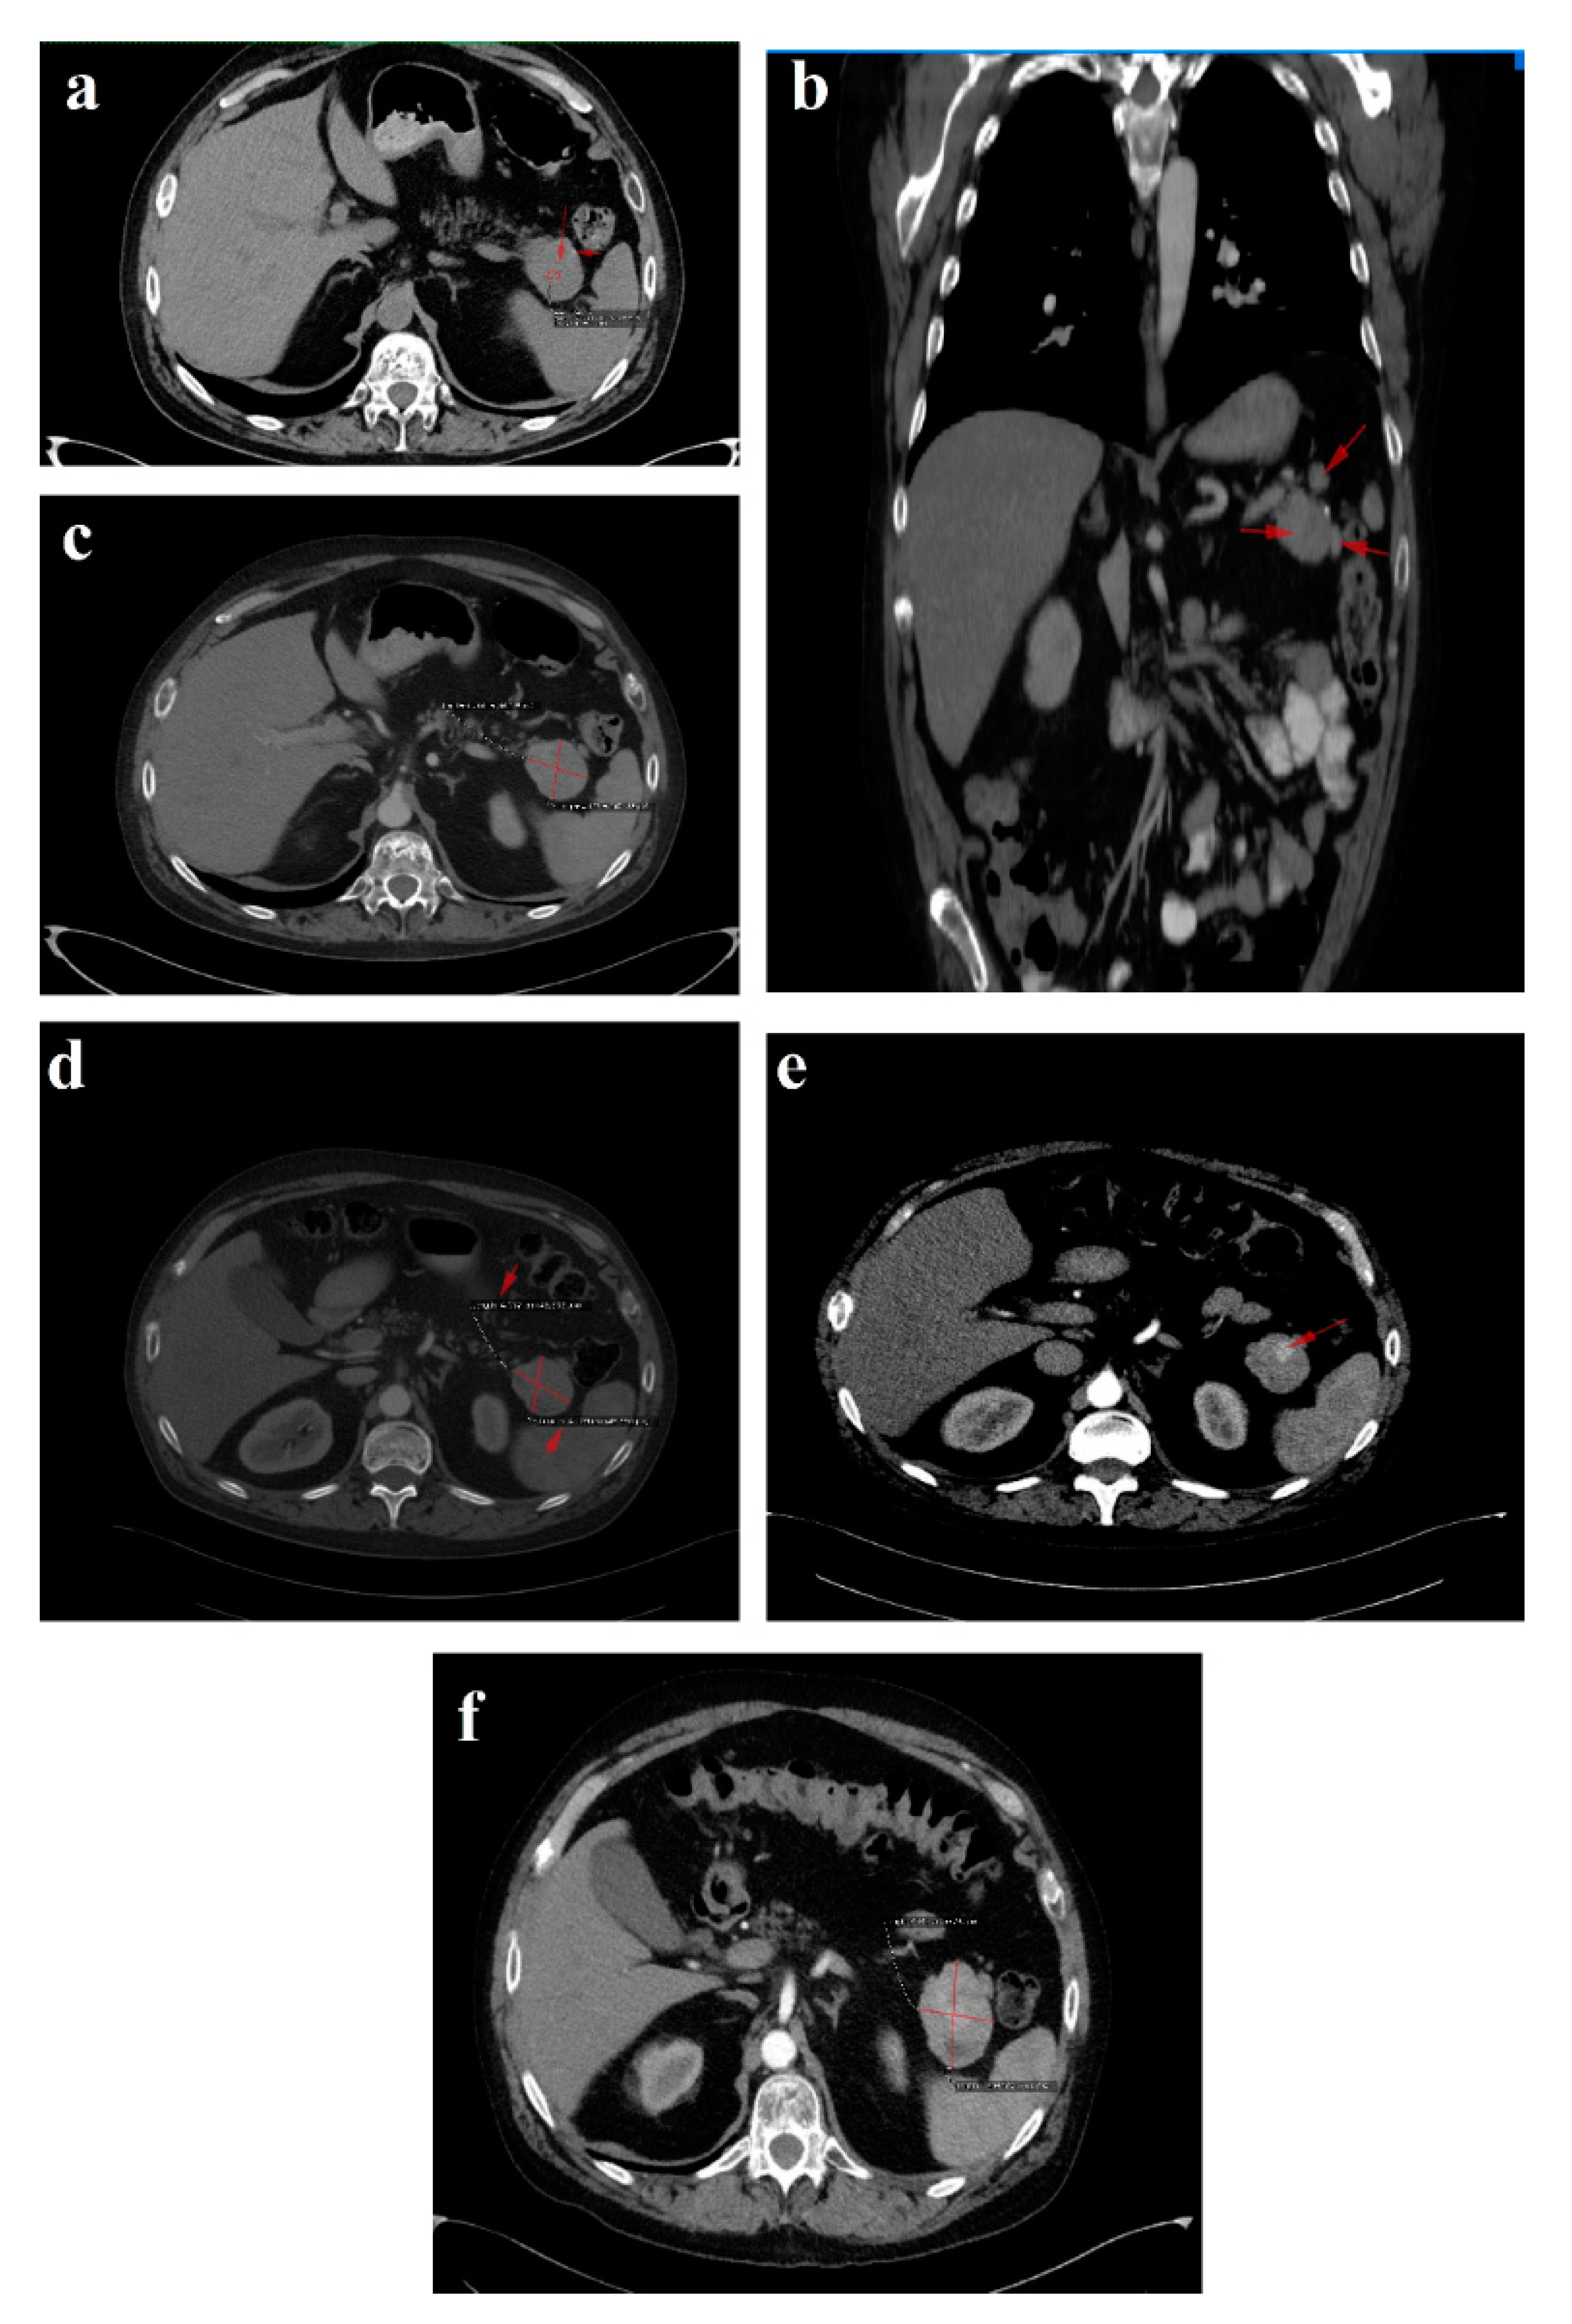

In January 2021, a follow-up CT reconfirmed locoregional tumor progression without apparent distal metastasis (Figure 6a–c), and a distal pancreatectomy and splenectomy were performed with a favorable outcome. An open approach with a bilateral subcostal incision was chosen. After opening the abdomen, a thorough examination of the peritoneal cavity was performed. We discovered a 6/5 cm tumor in the tail of the pancreas, without any vascular or retroperitoneal involvement. No liver or peritoneal metastases were present. We opted for a distal spleno-pancreatectomy in a standard fashion with a clockwise approach and individual splenic artery and vein ligation, ensuring a proper oncological safety margin on the pancreatic body. The pancreas was transected using monopolar cautery (Figure 7a) with pancreatic duct identification and clipping (Figure 7b), and the pancreatic stump was double sutured: the first was an overlapping horizontal mattress suture, and the second was a figure-eight suture (Figure 7c). Two drainage tubes were placed, the abdomen was closed, and the specimen was sent for pathology examination (Figure 7d). The postoperative course was uneventful. We checked the amylase level in the drained fluid on the third postoperative day and it was normal, which allowed us to exclude the pancreatic fistula. The abdominal ultrasonography performed did not show any collections, and the drainage tubes were removed. The patient was discharged on the eighth postoperative day.

The 3-month postoperative CgA, pancreatic polypeptide and glucagon plasma levels (193 ng/L) were normal. A follow-up CT revealed a few millimetric calcifications in the right lobe of an otherwise homogenous liver and a 105/53/48 mm fluid-filled encapsulated collection in the spleno-pancreatic space with contrast enhanced thin walls and surrounding surgical clips. Up to 40% of patients have fluid collections after distal pancreatectomy as a result of a small pancreatic leak, yet they usually are without clinical significance and very few of them will require percutaneous drainage. Since the patient was symptom-free, we decided to wait for a spontaneous resolution of the collection. No local tumor recurrence was detected. There was a slight enlargement of the lymph nodes in the perihilar hepatic region, a 15/13 mm portocaval adenopathy and an 8/7 mm newly-appeared nodule on the fissure of the round hepatic ligament (Figure 6d–f). Our MDT decided to resume SSA therapy and follow-up with the patient at 6 months.

Figure 6. Follow-up CT January 2021: (a) axial image-tumor progression; (b) axial venous phase with no vascular invasion; (c) coronal reconstruction venous phase, shows the fat plan between the mass and the vascular structures, indicating that the lesion is operable. Follow-up CT April 2021: (df) venous phase sagittal, coronal and axial reconstructions, respectively, showing fluid collection after the surgical removal of the pancreatic masses and the spleen. Red arrows and line indicate the lesions described in the figure legend; further information may be redundant.